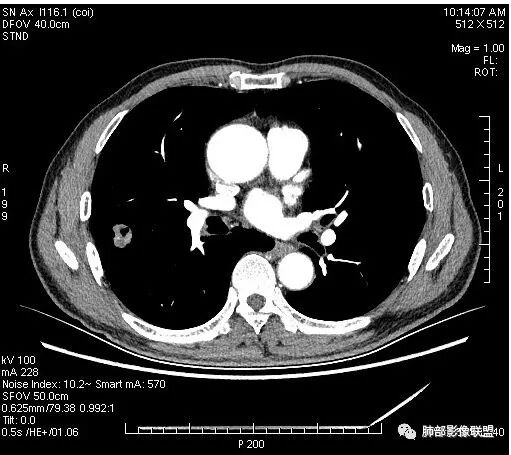

有血管穿行

部分地方膨隆,血管进入增粗

走行比较自然,破坏不明显,支气管没看见进去,不知道到底有没有

支气管堵塞

支气管截断明显啊,南大不指出,我没看出来。

右肺上叶结节,周围毛刺明显,其内有小炮征,分叶,强化中度,其内可见坏死,支气管有截断,考虑腺癌,鳞癌待排。病灶的上缘有一个小支气管进入,然后截断了

晨读:男,67岁,体检发现右肺结节。近圆形,支气管及伴行血管进入结节,进入结节后支气管堵塞,血管走形尚自然,结节内血管边缘凹凸不平。远端边缘见毛刺(软毛刺?)及分叶。见胸膜牵拉。实变中见空洞。整体膨胀感不明显。考虑炎性肉芽肿可能,隐球菌病可能性大。注意鉴别鳞癌、结核。

虽然良恶性征象都有,但是这个病灶增强后坏死比较明显,如果是恶性:腺癌这样大小的结节坏死很少见,只有低分化腺癌可以坏死,但是低分化腺癌这种大小一般会有周围转移表现(叶间胸膜结节,癌淋或者淋巴结明显肿大),如果是鳞癌,收缩力,坏死情况以及没有支气管截断都不太支持,而且结节远端有几个小结节样改变,大家可能认为是血管,但我觉得应该是卫星灶。所以觉得隐球可能较大。壁胸膜的牵拉线也没有引起胸膜凹陷,比较纤细,至于病理中的丝状物不一定是真菌菌丝。

我觉得穿过病灶的血管挺有特点,自然,没被吃掉,如果小细胞或者淋巴瘤可以,但后2个病有空洞不符

潘老师,这里在电脑上看:血管与伴行的支气管一起进入,如果是恶性,支气管应该在入口截断吧?@南边

这里支气管是进入到结节内以后才断的

这个大部分边缘稍微偏平直一点,血管走行非常自然,包括里面的空泡征样的,影子很干净,边界很光滑,都是些炎性特点。

4.病灶轻到中度强化。病灶内血管走行较完好,病灶旁血管局部显示粗大。

5.支气管关系不确定。